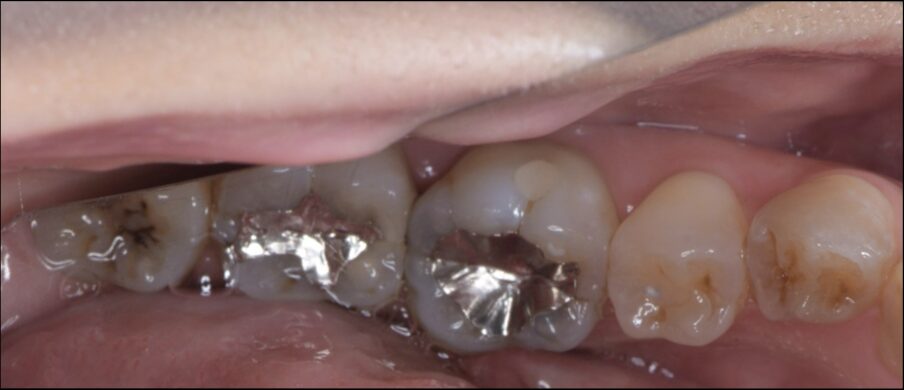

Before

レントゲンで虫歯が確認できた。

根管治療を行い、セラミッククラウンSET。